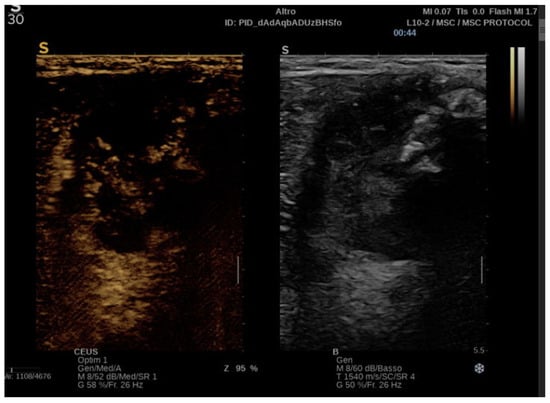

Malignant tumors exhibit chaotic, irregular, and excessive neovascularization due to angiogenesis, leading to heterogeneous, rapid, and intense contrast enhancement with irregular washout patterns. CEUS can precisely capture these characteristics, which are potential hallmarks of malignancy [40] (Figure 3).

Figure 3. CEUS of a malignant STT: arterial phase with both hyperenhancement and hypoenhancement due to necrotic areas.